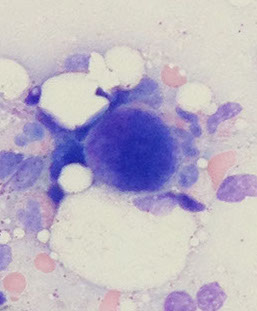

Low power morphologic abnormalities in MDS

Dys-ERYTHRO-poiesis = multinuclear, budding, megaloblastic, karyorhectic nuclei; PAS(+)/vacuoled cytoplasm

Dys-MEGAKC-poiesis = hypo-/non-lobate or multiple, separated nuclei and overall small size

Thrombocytopenia to thrombocytosis, giant forms, hypogranulation, micromegakaryocytes, functional abnormalities (abnormal aggregometry)

BM findings

Usually hypercellular marrow for age with erythroid hyperplasia, but may see normocellular or hypocellular marrow

Dysmegakaryopoiesis

Dysmegakaryopoisis

Meg dysplasia